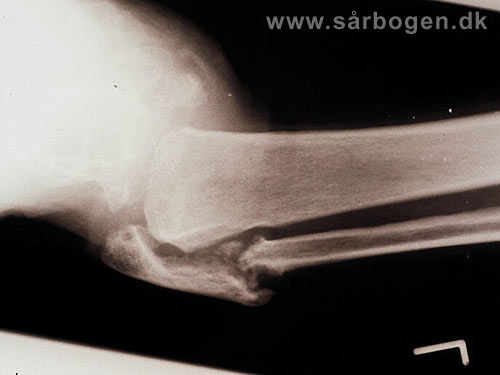

Charcot i ankel

Zoom

Charcot i ankel (rtg...